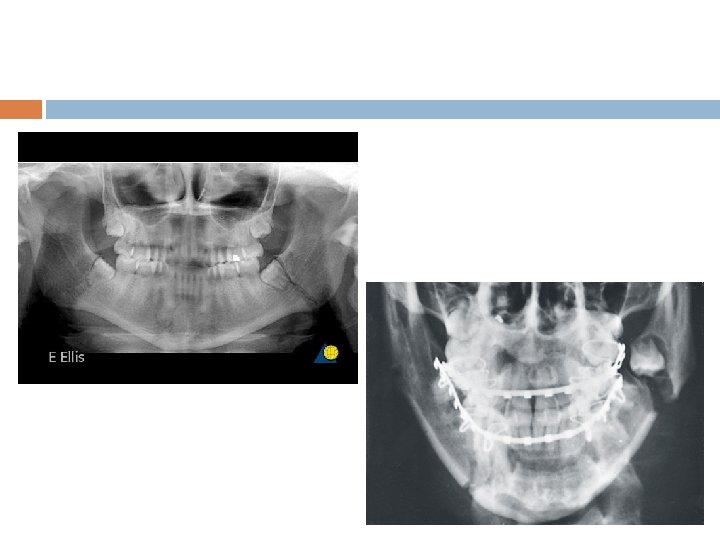

v v Reduced incidence of condylar fracture Increased Body Fracture Ellis, Moos and El Attar Busuito, Smith & Robson 1985 1986

Edentulous mandible fracture Scan

Body& Angle fract Comminut ed # Gunshot inj. Axe/shrp obj